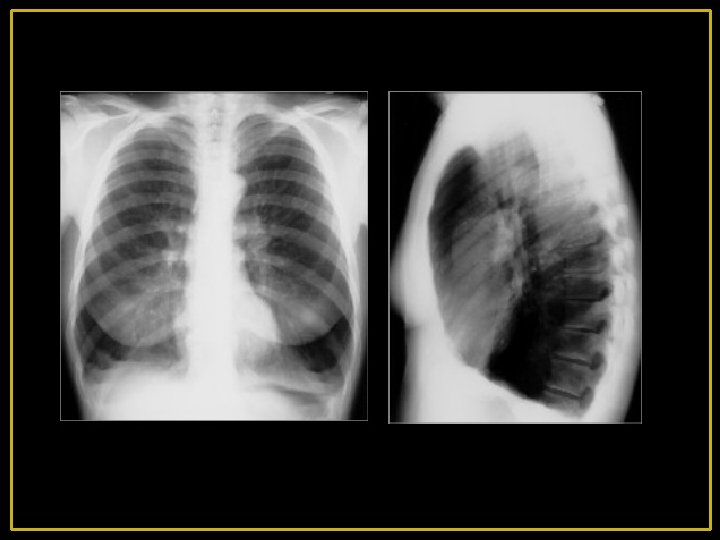

4 -Radiologie : - Distension thoracique majeure avec hyper clarté pulmonaire diffuse par raréfaction de la trame vasculaire. - L'existence parfois des bulles d'emphysème siégeant aux lobes inférieurs - Le cœur est petit, allongé, décollé de la coupole dit en « goutte » .

4’-Radiologie: -Distension thoracique modérée -Signes d'inflammation bronchique et pulmonaire prédominant aux bases. -Hyperclarté des sommets. -Cardiomégalie par retentissement pulmonaire CPC -Artères pulmonaires dilatées.